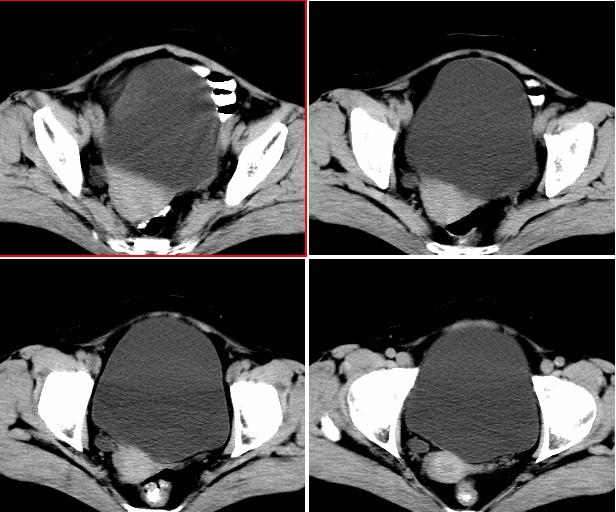

女,52岁,外伤后一小时入院,腹部b超示盆腹腔巨大无回声包块,右肾大小约208*107mm,追问病史,腹部逐渐隆8年余,无明显体重下降、消瘦、黑便呕血史,无大便性状改变,2年前已停月经,有高血压病史8年余,pe:血压180/100mmhg,全身皮肤粘膜无黄染、苍白,全身浅表淋巴结无肿大,腹部膨隆,呈蛙腹,可触及腹部有一14*15cm大小包块,质软,边界清楚,移动度可,无压痛,叩诊呈浊音。辅助检查:肝功能白蛋白43g/l球蛋白35.2g/l余指标正常,血糖电解质凝血四项正常。血常规hb115g/l白细胞13*10/9/l n0.85肾功能bun6.53mmol/l cr124umol/l.

右侧后腹膜巨大囊性肿块影阴,边缘清晰,内见膜状分隔,均匀水样密度,右肾影阴消失,囊块所到区域脏器受挤移位,右侧输尿管扩张,应该考虑:右肾重读积水,巨大肾囊肿不除外。引发肾性高血压。

腹部巨大囊性占位,膨胀性生长,边界光整,囊内容物为水样密度,其内可见多发分隔,纵观所有层面,正常右肾未见,考虑为来源于右肾的巨大多房性肾囊肿(多房性囊性肾瘤)可能性大。

该病来源和病因不明,儿童为先天性,多在5岁以下发病,成人多见于40-70岁女性,ct表现:单房或多房囊性病灶,有厚的囊壁,大部分有分隔,部分可出现环形、沙粒状钙化。

腹部巨大囊性占位,膨胀性生长,边界光整,囊内容物为水样密度,其内可见多发分隔,右恻输尿管全程扩张,纵观所有层面,正常右肾未见,考虑为来源于右肾的巨大多房性肾囊肿可能性大。

反推一下:1.那么重的积水,引起积水的原因大部分是右侧输尿管有梗阻,排出受阻。右侧输尿管应该也是重度扩张才对。2.如果是肾积水,而且是右侧输尿管问题引起,那么病人肯定有相应的临床症状:比如输尿管结石引起的血尿、剧痛等症状,至少也会急性发作病史。另,本例显然不需要考虑输尿管癌,膀胱也挺好,更没有无痛性血尿病史。病人8年多没有其他的不舒服,只是腹部日渐膨隆,临床症状显然不支持。3.如果是重度肾积水的话,应该可以看到被压缩的肾皮质,即使很菲薄也多少会有显示的。

右肾明显扩大,皮质菲薄,间隔细,右输尿管全程扩张,右肾重度积水,原因应重点查输尿管膀胱接合处。

右侧巨大囊状无功能肾,输尿管积水.右侧积水肾旁囊性病灶应该是左侧卵巢浆液性囊腺瘤.